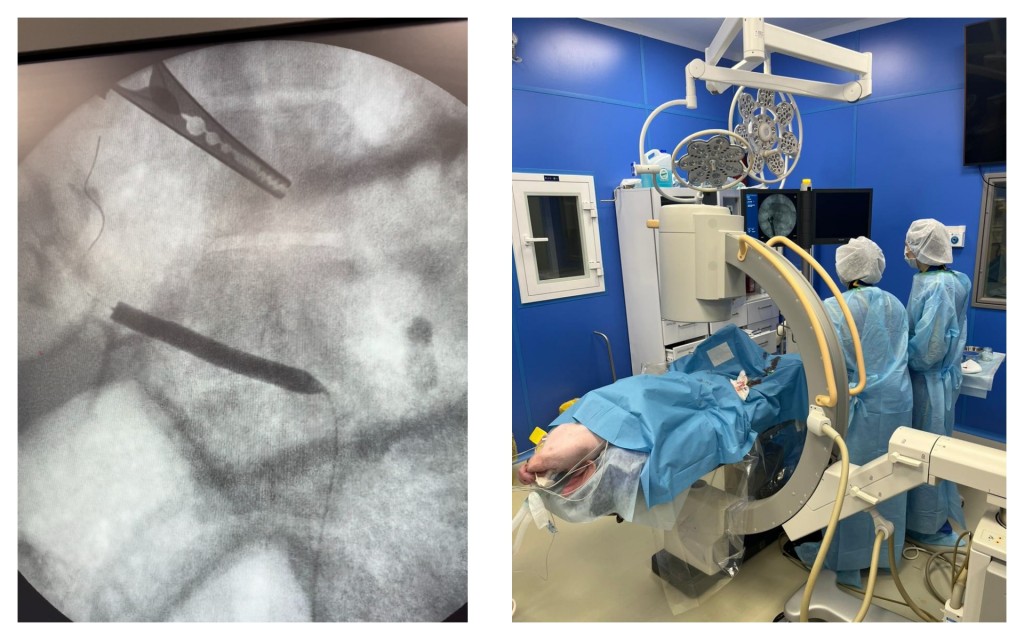

- Мастер-класс по применению браншированных стент-графтов при лечении аневризма торакоабдоминального отдела аорты

- Мастер-класс по применению фенестрированных стент-графтов при лечении юкстаренальных аневризм брюшной аорты

2024 год

- Международный мастер-класс по эндоваскулярному лечению аневризм торакоабдоминального отдела аорты с использованием методов интраоперационной фенестрации с участием экспертов из Китая